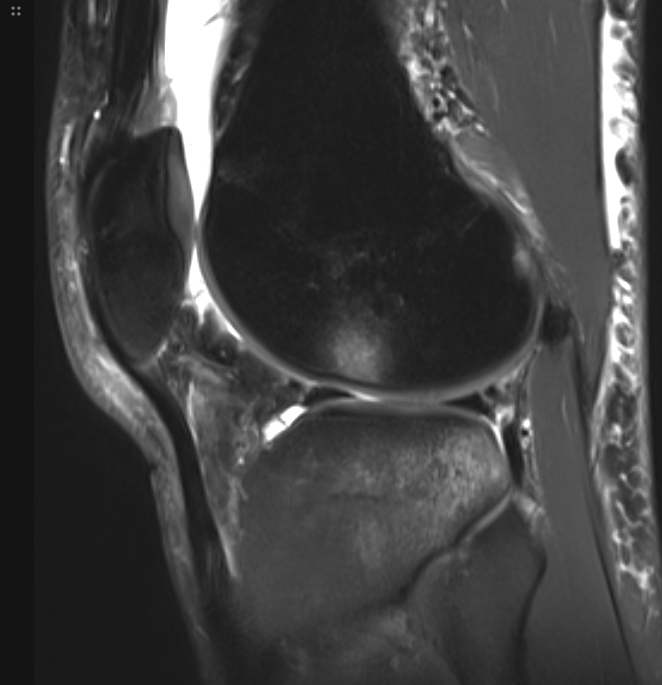

3. Pivot shift bone bruising pattern